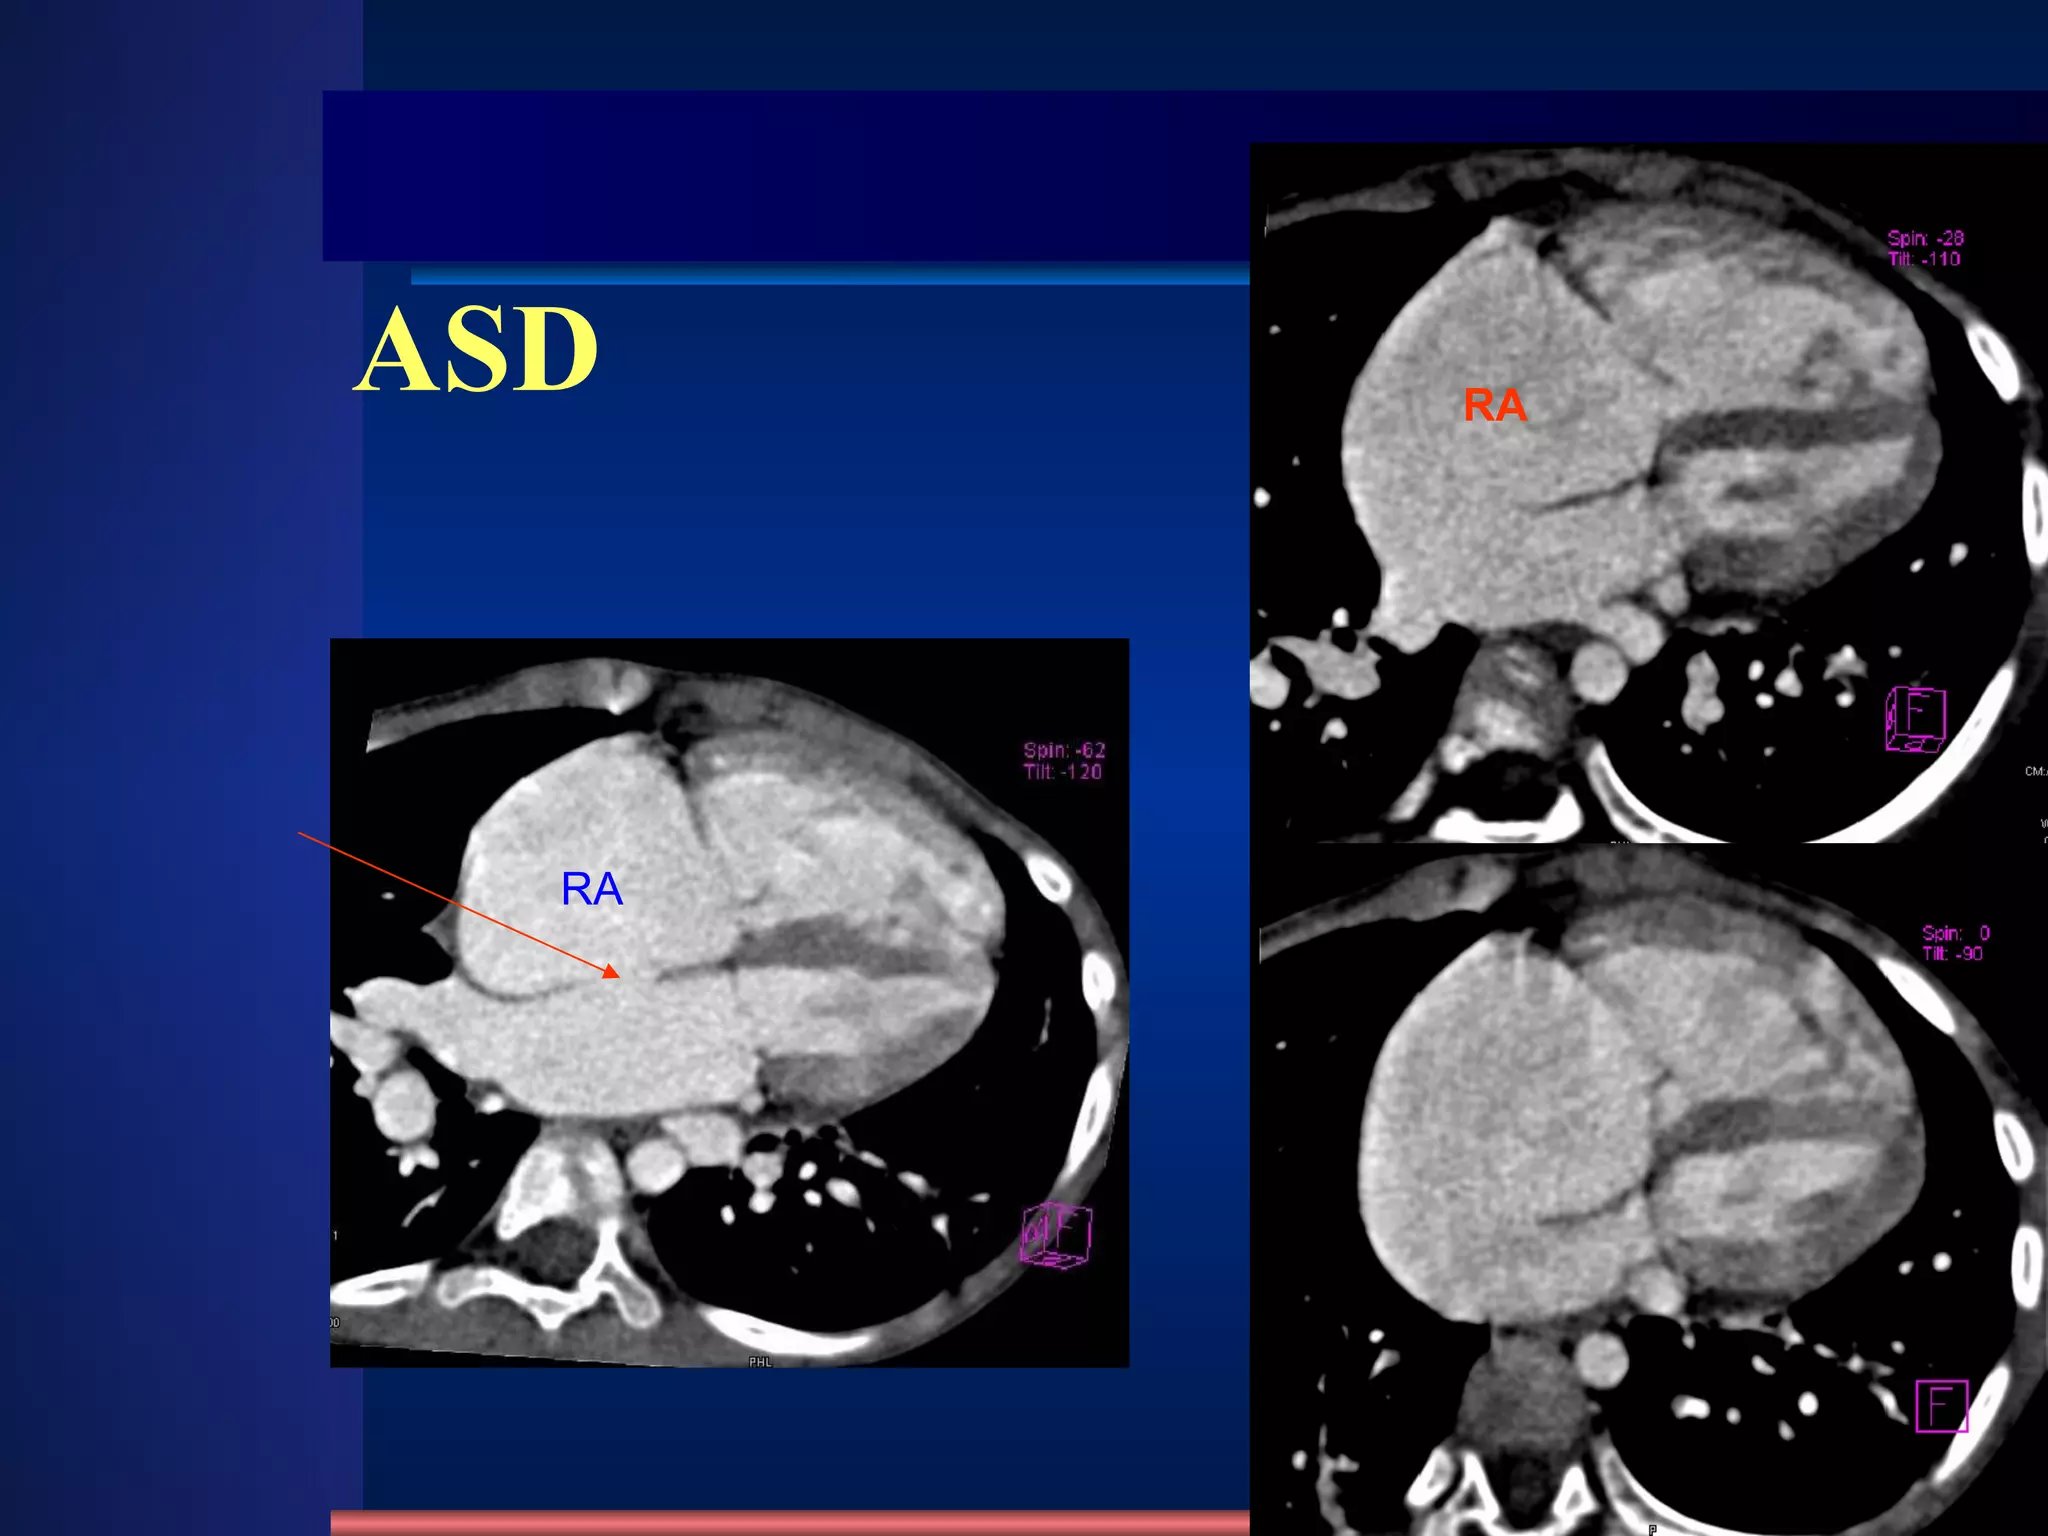

ASD Clinic mostly adult  SM on the 2th-3rd intercostal of the left sternal border Change of hemodynamics X-ray appearance Cardiomegaly , “mitral configuration” RA & RV↑ ,  RA↑ ↑   obviously Pulmonary artery segment bulge  , hilum angiectasia, hilum dance pulmonary blood flow↑ ↑. PAH in later stage LA do not enlarge, LV and aorta shrink /231 4 type: Ostium primum , ostium secundum Sinus venosus , coronary sinus Fossa Ovalis defect 80~90% Atrial septal defect methods normal abnormities diseases

ASD RA RA

ASD aorta shrink RA & RV↑ ,  RA↑ ↑   obviously RA RV PA Aorta svc

ASD RA & RV↑ ,  RA↑ ↑   obviously

ASD /231 Enlargement of RA methods normal abnormities diseases RA RV PA Aorta svc